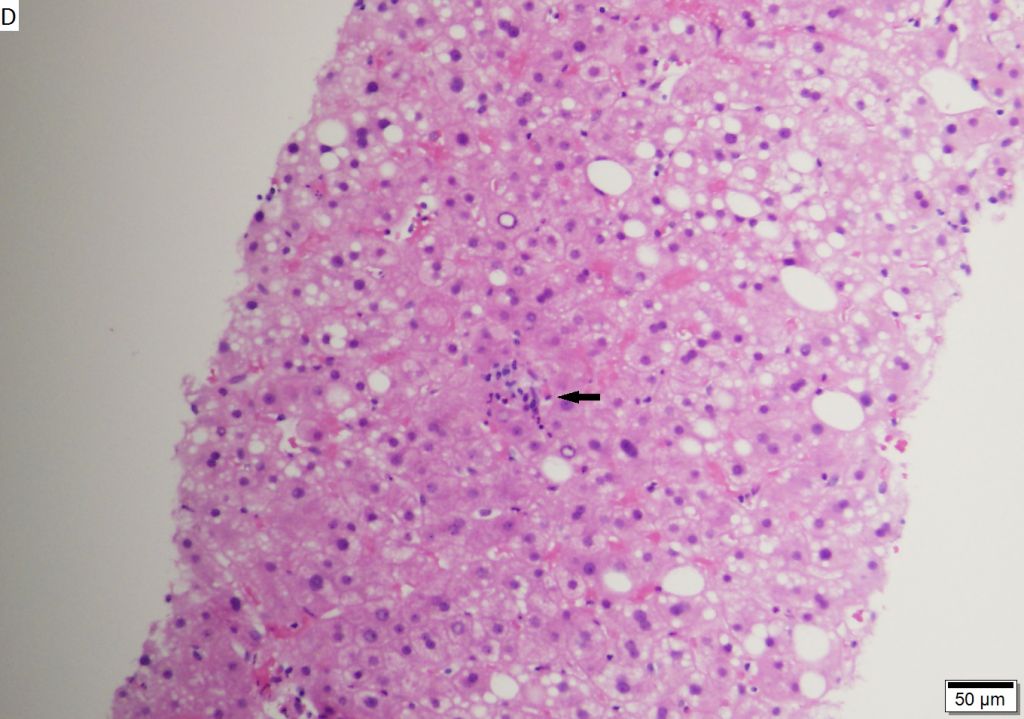

The way in which the virus affects the patient’s liver is a kind of a real action movie or thriller. The pathogen reaches the liver with the blood flow. There is a special type of polypeptide on the surface of the liver that is vulnerable to the large hepatitis B protein. By binding the polypeptide, hepatitis gets into the center of cell while taking off its envelope and releasing its DNA on the move. Figuratively speaking, the virus cracks and captures the cell using the polypeptide as a lock pick. This process extends over the whole liver with time and usually takes from 3 to 6 months.

Despite such ruthless capture, the virus does not kill the liver cells. This is done by our immune system that activates T-lymphocytes or killer T-cells. It is they who inflict critical damage on the organ. The inflammation also acts as a signal for other immune cells making the situation in the liver tissues even more difficult. The patient may be not aware of the disease for a long time, because the processes taking place in the liver may not manifest themselves during the first six months.